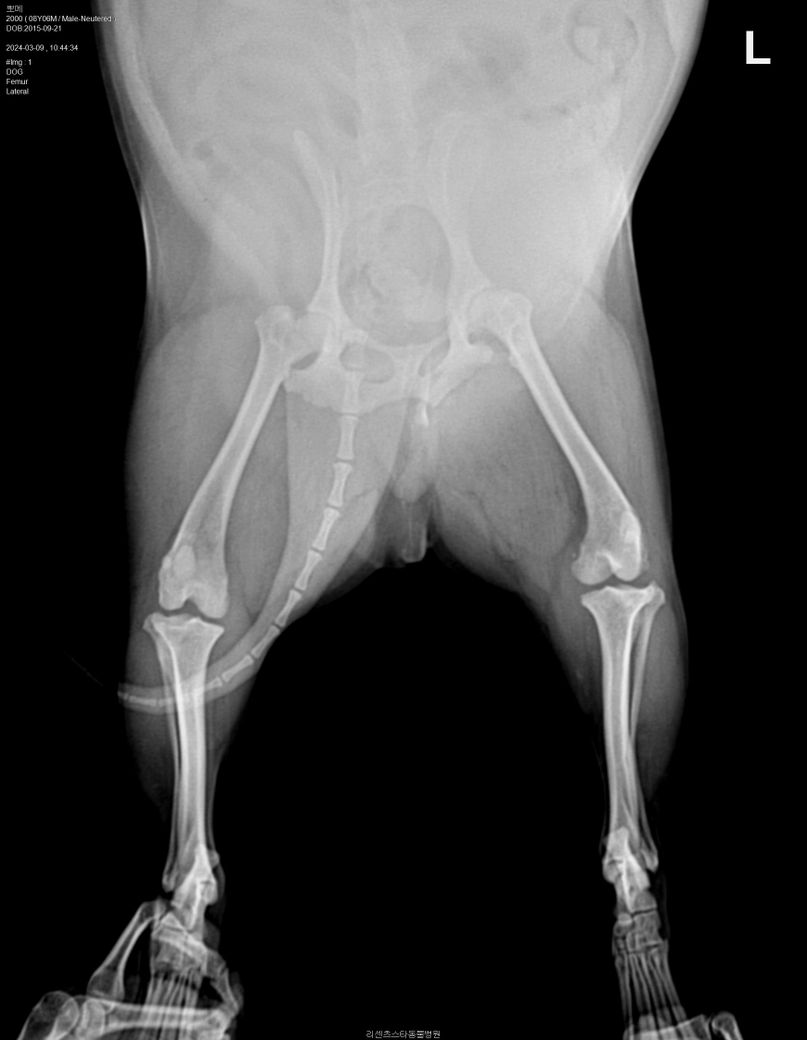

인대파열인가요?(엑스레이 판독 부탁드립니다)

어제 소파위에서 이리저리 뛰어 다니다 갑자기 소리를 내며 왼쪽 다리에 고통을 느끼는 것 같았습니다. 하루가 지난 지금도 왼쪽 뒷 다리는 계속 들고 다닙니다. 만졌을때 고통스러워 하지는 않습니다.

동네 병원에서 엑스레이를 찍었는데 인대 파열이 의심 된다고 합니다. 엑스레이 자료를 주시면서다른 전문 병원으로 가라고 하시네요. 여기 전문가선생님들께서 엑스레이 자료를 보시고 의견을 주셨으면 좋겠습니다

방사선 촬영만으로는 십자인대 단열을 확진할 수는 없겠지만 지금 왼쪽 다리를 보시면 아예 정강 뼈가 전방으로 변위가 심한 것을 보면 십자인대 완전 단열을 가능성이 매우 큽니다.

경골이 전방변위 되어 있으며 관절낭이 심하게 종창되어 있습니다. 전형적인 십자인대 단열 혹은 부분단열 소견으로 주치의의 판단이 옳으니 의심하지 말고 주치의의 의견을 따르시기 바랍니다.